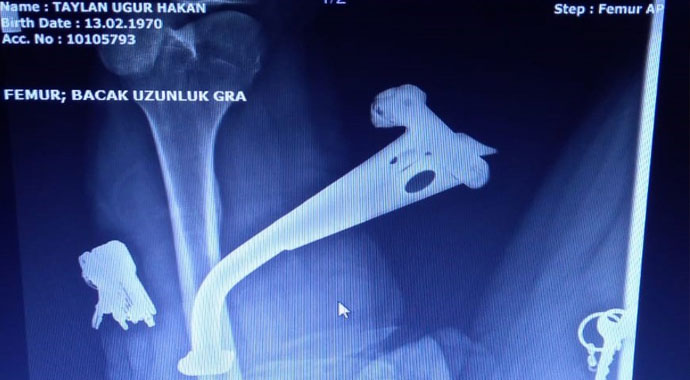

İzmir'in Çeşme ilçesindeki motosiklet kazasında, bacağına motosikletin ayaklığı saplanan Uğur Hakan Taylan, Çeşme Alper Çizgenakat Devlet Hastanesi'nde geçirdiği operasyonla ayaklıktan kurtarıldı.

Çeşme ilçesinde, motosikleti kullanan sürücü mıcırlı yolda direksiyon hakimiyetini kaybetti. Motor metrelerce sürüklenirken, kazada motosikletin ayaklığı Uğur Hakan Taylan'ın baldırına saplandı. Motoru kullanan yeğeniyle birlikte baldırına saplanan ayaklığı çıkarmaya çalışan Taylan, başarılı olamayınca 112 Acil Sağlık'tan yardım istedi. Olay yerine gelen ekipler, itfaiyeden yardım isteyerek, motosikletin ayaklığını kestirdi.

Ambulansla Çeşme Alper Çizgenakat Devlet Hastanesi'ne kaldırılan Uğur Hakan Taylan'a hastanede ilk müdahale yapılırken, Ortopedi ve travmatoloji uzmanı Op. Dr. Osman Refik Çetin de hastaneye gelerek, Taylan'ı ameliyata aldı. Bu duruma sağlık çalışanları da şaşırdı. Taylan'a lokal anestezi yapılarak, baldırına saplanan motosiklet ayaklığı çıkarıldı. Op. Dr. Çetin, Uğur Hakan Taylan'ın baldırındaki sinirlerin ve damarların zarar görmediğini belirterek, hastanın iyi durumda olduğunu ve birkaç gün sonra da dikişlerinin alınacağını söyledi.